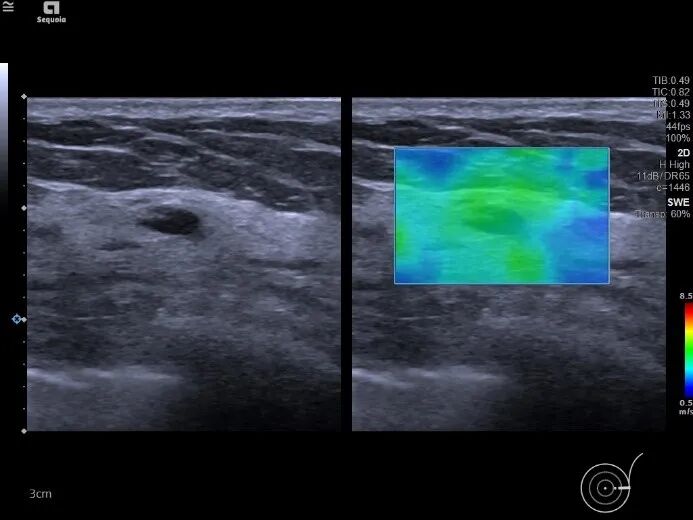

常规超声显示,左乳4点处可见一个低回声实质团块,诊断为乳腺MT(BI-RADS 4C)。左乳外上近3点处另可见一个6×3mm的低回声实质小结节,边界尚清晰,未见明显包膜,内回声分布尚均匀,与MRI显示的位置一致。

彩色多普勒超声显示,该结节内部可见较丰富的短线状彩色血流信号。

然而剪切波超声弹性成像VTIQ进一步评估发现,该结节质地较软,内部呈蓝绿色。